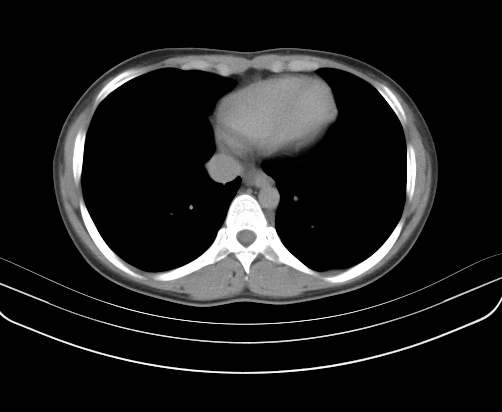

胸部